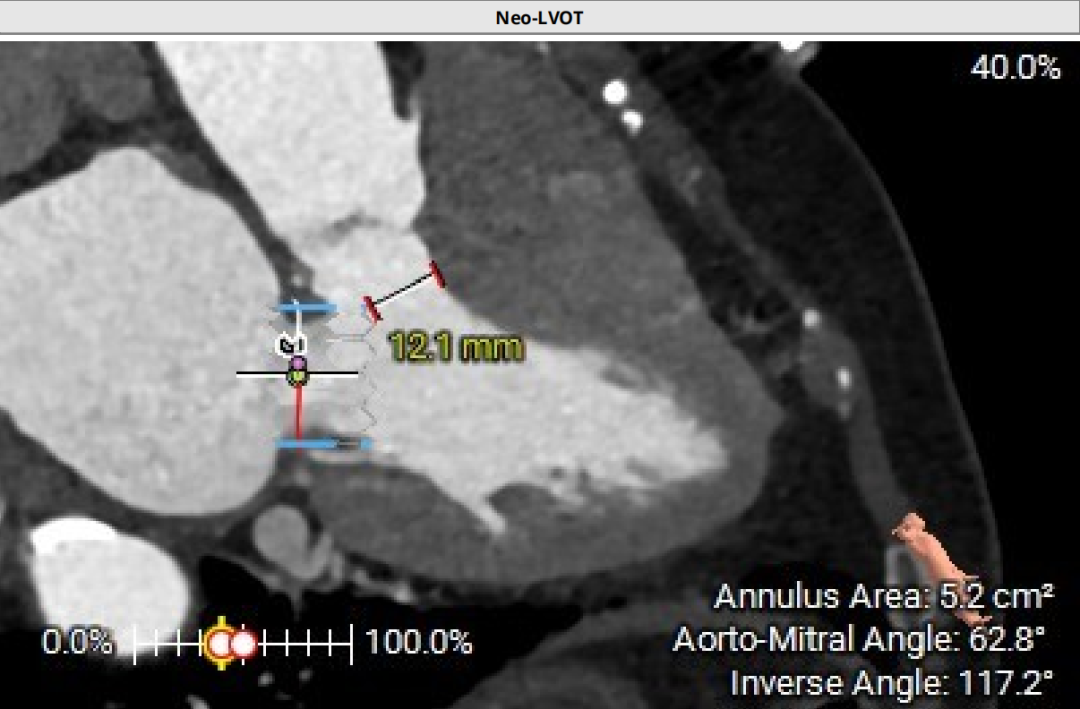

左房53×48mm,靠后下的房间隔穿刺点距二尖瓣高度17.9mm。患者房间隔显著增厚、钙化,房间隔穿刺点较低,考虑房间隔穿刺及器械到位较为困难。

心尖投影位于第六肋间,心尖部心肌厚度4.3-5.2mm

谷兴华教授团队组织经过多学科讨论,认为:因患者71岁,基于全生命周期管理的理念,需要选用较大尺寸、更大EOA的介入瓣膜,以备第二次MVIV。最终的手术方案为:经心尖入路,先用25#Renatus标准压力释放,再用24mm的Atlas Gold球囊高压后扩,将25#原人工Mosaic生物瓣环扩断。